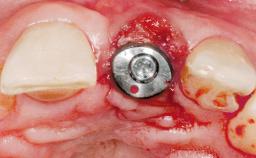

Immediate Flapless Placement of an Implant in a Maxillary Right Lateral Incisor Site

This 43-year-old male patient, a non-smoker, came to our practice because of a fracture of tooth 12 caused by a bicycle accident. Due to the combined para- and infrabony crown and root fracture, tooth extraction, and subsequent implant placement were suggested to the patient as the therapy of choice. The patient had high esthetic expectations with regard to the treatment outcome and asked for an immediate fixed provisional restoration. His individual esthetic risk profile summed up to a medium esthetic risk.

Placement Protocol Immediate implant placement

Tooth Site Maxillary incisor or canine

Socket Morphology Single-root socket

Socket Integrity Sufficient, with intact bone walls

Loading Protocol Immediate